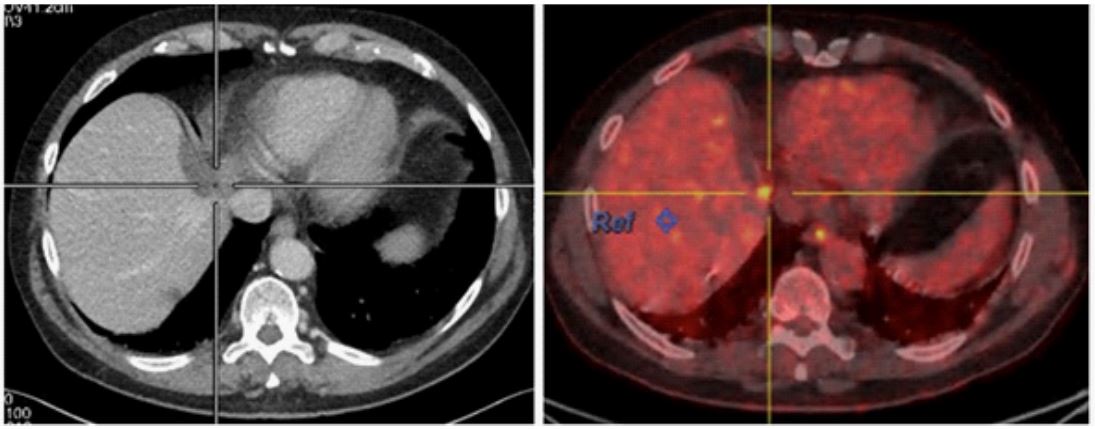

Eleven months later, a metachronous metastasis was detected on CT-scan (segment VI), while stigmata of resection around segment VIII persisted. The subsequent PET-CT excluded extra-hepatic disease and revealed not only a pathologic metabolic activity in segment VI (SUV 7,5) but also in segment VIII at the site of previous liver resection (SUV 8,3) (Figure 1A).

After second line neoadjuvant chemotherapy, a control PET-CT identified a complete metabolic response of the tumour in segment VI, and partial response (SUV 3,9) in segment VIII (Figure 1B)

Figure 1: Representative images of PET-CT metabolic activity in the site of previous wedge resection on segment VIII (A) at diagnosis (SUV 8,3) (B) after neoadjuvant therapy (SUV 3,9)